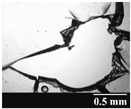

| Capsule Type | Time | RSC (%) | Area of Capsule Puncture (mm2) |

|---|---|---|---|

| GEL | Before storage | 15.26 ± 0.18 | 0.60 ± 0.16 |

| 1 month | 10.31 ± 0.21 | 0.74 ± 0.11 | |

| 3 months | 7.23 ± 0.28 | 1.01 ± 0.28 | |

| 6 months | 6.68 ± 0.12 | 1.14 ± 0.38 | |

| GEL-PEG | Before storage | 11.87 ± 0.09 | 0.54 ± 0.10 |

| 1 month | 10.68 ± 0.32 | 0.84 ± 0.12 | |

| 3 months | 8.74 ± 0.15 | 0.89 ± 0.14 | |

| 6 months | 7.12 ± 0.12 | 0.92 ± 0.07 | |

| HPMC | Before storage | 5.98 ± 0.11 | 0.79 ± 0.05 |

| 1 month | 5.45 ± 0.09 | 0.79 ± 0.04 | |

| 3 months | 4.84 ± 0.13 | 0.86 ± 0.08 | |

| 6 months | 4.62 ± 0.02 | 0.88 ± 0.03 |